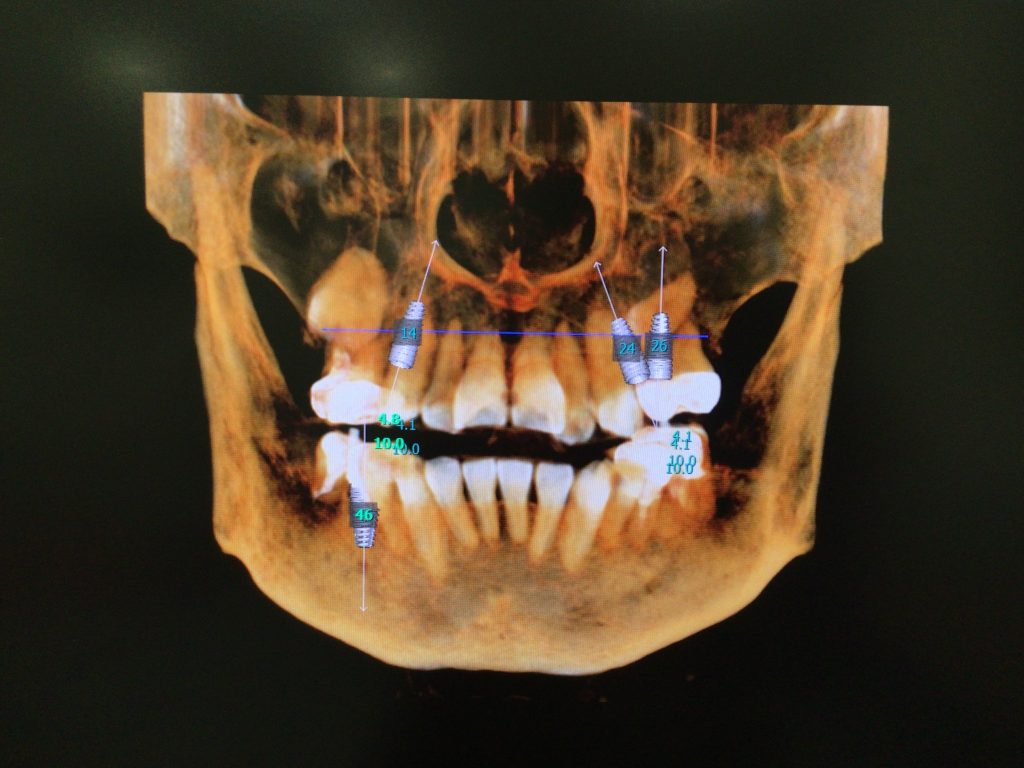

当院ではインプラント検査時にCT撮影を行なっています。

埋入部位に骨が十分にあるかどうか、神経がどこを通っているかなどの確認をしてインプラント体を入れる位置などを決めています。